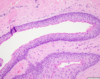

You perform an incisional biopsy on a unilocular radiolucent lesion of the left maxilla in the lateral incisor-canine area which is causing divergence of these tooth roots. A representative image of the biopsy specimen is shown below. What is the best diagnosis? A. Lateral periodontal cyst B. Odontogenic keratocyst C. Glandular odontogenic cyst D. Ameloblastoma E. Calcifying odontogenic cyst

B. Odontogenic keratocyst The image shows the architecture of a cyst, including a lumen, epithelial lining, and fibrous connective tissue wall, therefore choice D is incorrect. The exact type of cyst is determined by the features of the epithelial lining. The epithelial lining shown is ~6-8 cell layers thick, has a palisaded basal cell layer, and is covered by a corrugated surface of parakeratin. Therefore, the correct answer is B. A lateral periodontal cyst (A) will have a thinner lining (1-3 cells thick) with focal thickenings and no keratin. A glandular odontogenic cyst (C) will have a lining of variable thickness and other features including mucous cells, apocrine snouting, microcysts, and cilia. A calcifying odontogenic cyst (E) will have aberrant keratinocyte formation known as “ghost cells.”